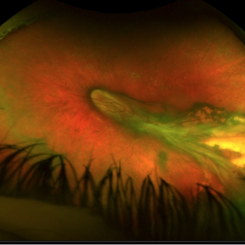

Ocular Toxocariasis with Peripheral Granuloma

8-year-old boy with a retinal fold secondary to peripheral toxocara canis granuloma localized on the superior retina.

Photographer: Corina Skrzek

Imaging device: Optos California

Condition/keywords: toxocariasis